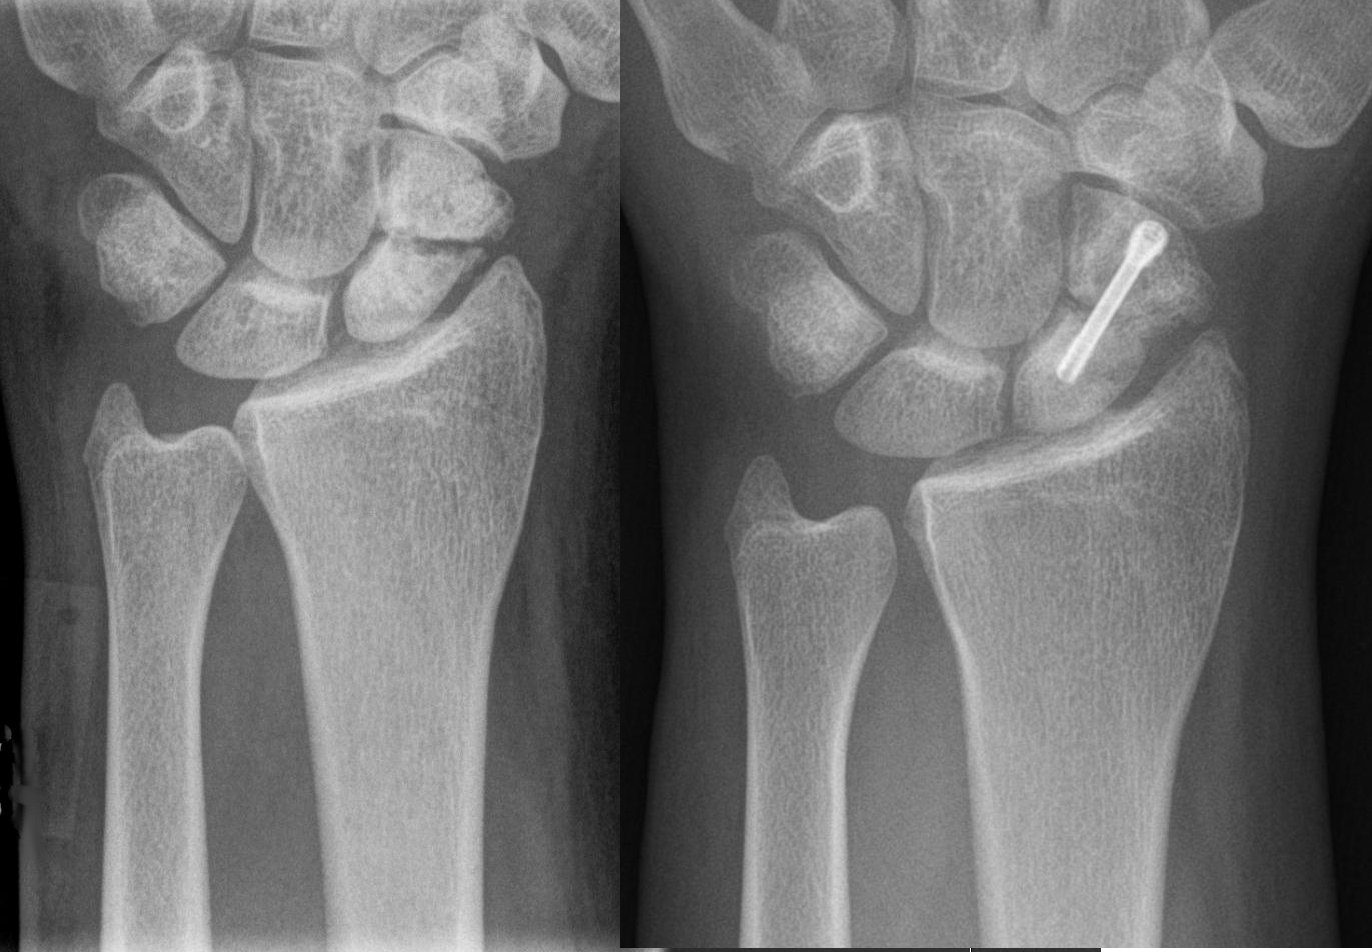

일반적으로 골절된 뼈의 병력이 확실하다. 불유합이 있는 환자는 골절 부위의 지속적인 통증을 호소하며 골절 부위에서 비정상적인 움직임이나 딸깍거리는 소리를 느낄 수 있다. 골절된 뼈의 X-선판은 골절 부위에서 방사선 투과선이 확인된다. 불유합의 경우 골절선이 계속 보이거나 골절 끝 부위에 경화가 확인된다. 또한 뼈가 낫는 데 형성되는 작은 뼈 조직인 가골 형성이 없거나, 가골이 형성되었어도 골절 사이를 연결하지는 않는다.[1]

X-ray 판독에 의문이 있을 경우, 스트레스 X-ray, 단층 촬영 또는 CT 스캔을 사용하여 확인할 수 있다.[1]

손상된 뼈의 특정한 해부학적 위치는 골절 치유 능력과 관련이 깊다. 대부분 골절 부위의 혈류에 따라 그 차이가 발생한다. 예를 들어 장관골의 골간단부, 골반뼈 등은 풍부한 혈류를 가지는 곳으로 골절 치유가 잘 이루어진다. 장관골의 골간부는 그 중간적 위치에 속하는데, 혈류가 많지는 않으며 골간단부에 비하여 골절의 치유 기간이 길고 불유합의 가능성이 높다. 특히 거골 경부, 대퇴골 경부, 손의 주상골[25] 등은 비교적 골절에 의해 쉽게 손상을 받는 부위이며, 혈류가 적어 불유합, 무혈성 괴사 등 합병증의 가능성이 높다.

불유합의 진단은 임상의가 추가적인 중재 없이는 뼈가 더 이상 치유되지 않을 것이라고 판단할 때 내려진다. 미국 식품의약국(FDA)은 불유합을 최소 9개월 이상 되었고, 지난 3개월 동안 방사선학적 치유 징후를 보이지 않은 골절로 정의한다.[9] 컴퓨터 단층 촬영(CT)은 골절 부위를 더 자세히 보여주며, 골절 부위의 치유 정도를 평가하는 데에도 사용될 수 있다. 혈액 검사를 통해 환자의 칼슘과 비타민 D와 같은 영양소 수치가 적절한지 평가할 수 있다. 또한 혈액 검사로 ESR(적혈구 침강 속도) 및 CRP(C-반응 단백)와 같은 감염 지표를 확인할 수도 있다.[7]